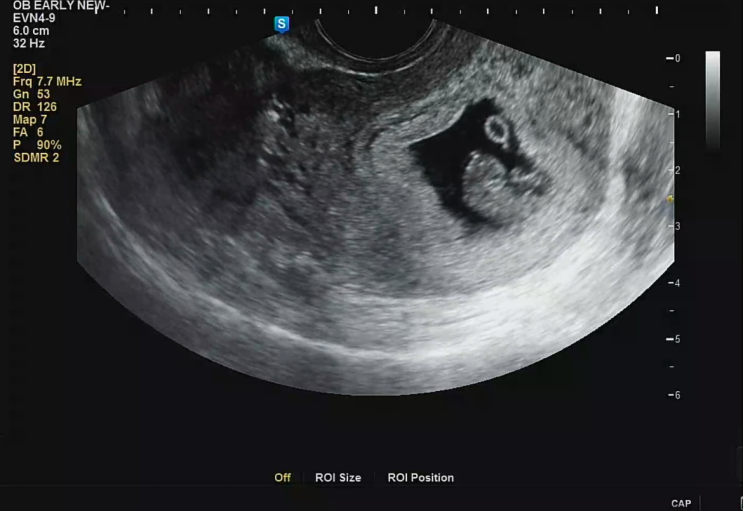

임신 8주차, 우리에게 너무 빨리 찾아온 아기

성격 급한 나를 닮아서 그런가 우리의 연애, 신혼 라이프는 한순간에 스킵시켜버린 우리아기 나는 운동도 ...